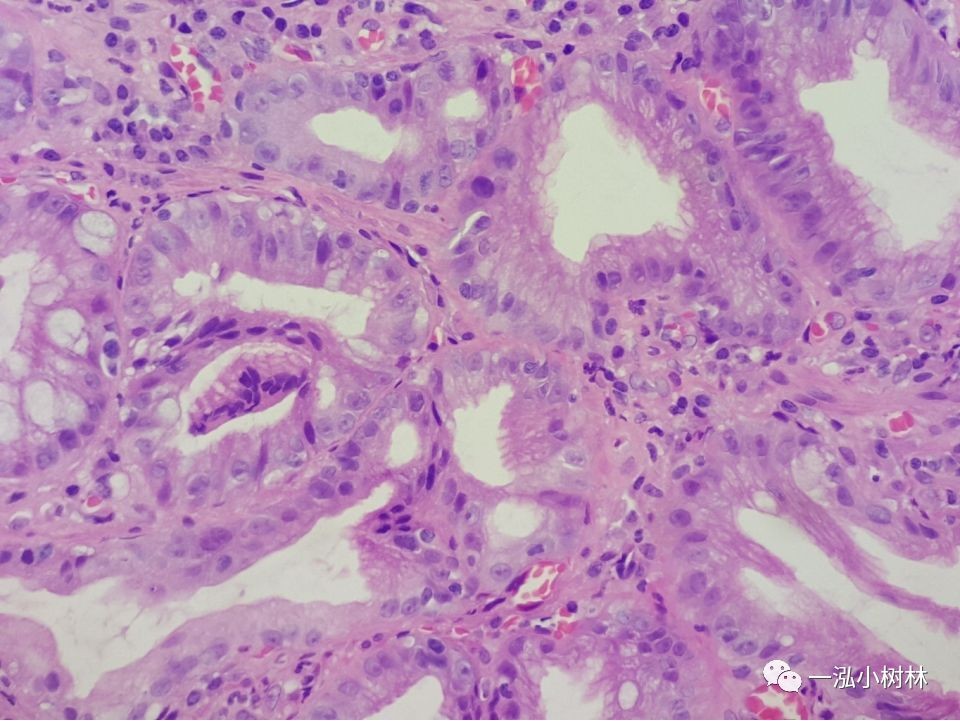

例4

女性,42岁,萎缩性胃炎+肠化+Hp感染

亮蓝嵴(LBC):位于上皮细胞表面呈脑回样结构脊部的纤细、蓝白色的腺样结构。特征:NBI才能观察到。NBI显示亮蓝色细线样反光,位于上皮细胞边缘。提示肠上皮化生刷状缘。是内镜诊断胃黏膜肠上皮化生的有效标志。